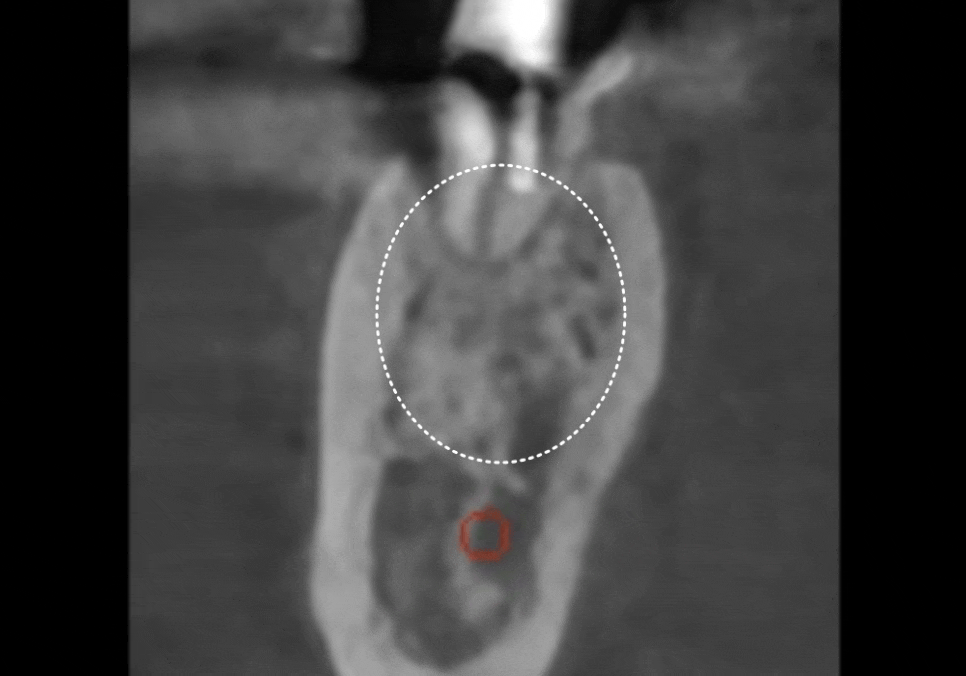

CT를 살펴볼게요~

241015

혹시 앞서 보여드렸던 환자와의

차이점을 눈치채셨나요?

빨간 동그라미로 표시한 하치조 신경인데요.

이 신경과 뿌리 끝 사이의 뼈가

확실히 뼈가 꽉 차 있고

하얗게 밀도가 높은 느낌이 들죠~?

이 환자분은 뿌리 끝에 염증이

있었던 게 아니라,

치아 자체가 약해 뿌리만 부러진 상태였기에

주변 뼈는 아주 건강하게 남아 있었습니다.

이렇게 토대가 튼튼하다면

치아를 뽑는 당일 임플란트를 바로 심을 수 있어요.